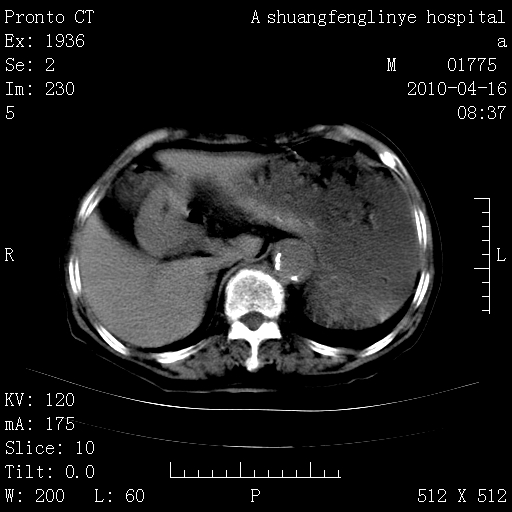

标题: CT25784:咳痰、请会诊!结核? [打印本页]

标题: CT25784:咳痰、请会诊!结核?

陈旧性结核,胃腔扩大,脾脏受压后移

慢支肺气肿,左上陈旧性结核,主动脉冠脉钙化

典型 夹层动脉瘤。 内膜瓣钙化移位

1)左肺上叶结核(纤维、增殖病灶)。2)冠状动脉及主动脉钙化。

1)左肺上叶结核(纤维、增殖病灶)。2)冠状动脉及主动脉钙化。肺动脉高压